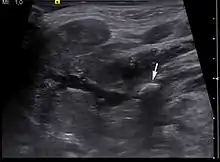

Ultrasound image of sialolithiasis

Diagnosis is usually made by characteristic history and physical examination. Diagnosis can be confirmed by x-ray (80% of salivary gland calculi are visible on x-ray), by sialogram, or by ultrasound.